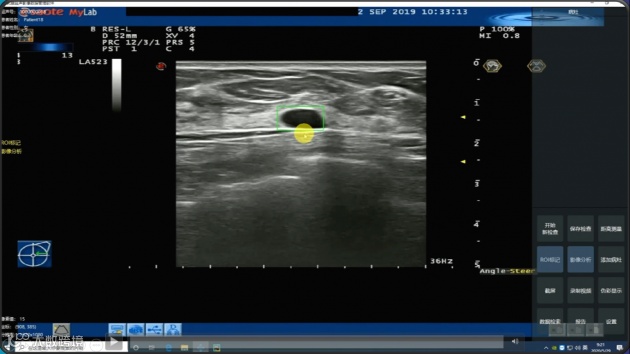

(二) 医准智能 乳腺超声智能分析系统

医准智能推出的乳腺超声智能分析系统,基于三维超声动态实时识别的AI分析,该系统在不改变现有超声设备和医院工作流程的基础上,利用神经网络架构搜索方法(NAS)对超声信号进行实时智能分析,实现实时病灶检出,对病灶进行自动分割及良恶性分析。这是国内首个针对超声设备的AI检测系统,将乳腺智能检测推进到视频实时的AI3.0时代。